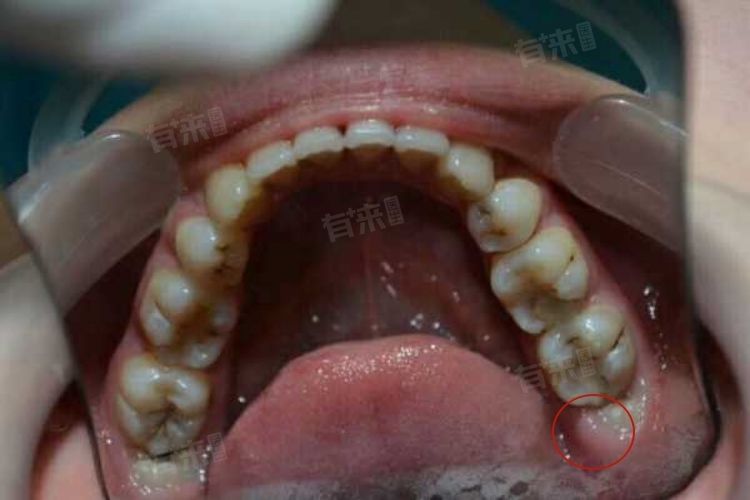

拔完智齿后的饮食要遵循从流食到半流食,从清淡到逐渐丰富的原则,避免食用辛辣、过硬、过热或过冷的食物,这样才能确保创口顺利愈合,减轻疼痛和不适,使身体尽快恢复正常。